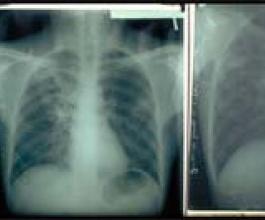

O distrito de Bragança é o segundo do País onde se registam menos casos de tuberculose. Estas conclusões foram divulgadas pela Sub-Região de Saúde de Bragança (SRSB), na passada quinta-feira, numa conferência de imprensa realizada no âmbito do Dia Mundial da Tuberculose, celebrado no passado sábado.